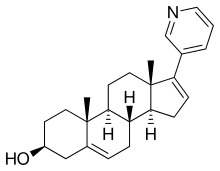

Abiraterone acetate, also known as 17-(3-pyridinyl)androsta-5,16-dien-3β-ol acetate, is a synthetic androstane steroid and a derivative of androstadienol (androsta-5,16-dien-3β-ol), an endogenous androstane pheromone.[41] It is specifically a derivative of androstadienol with a pyridine ring attached at the C17 position and an acetate ester attached to the C3β hydroxyl group.[41] Abiraterone acetate is the C3β acetate ester of abiraterone.[41]